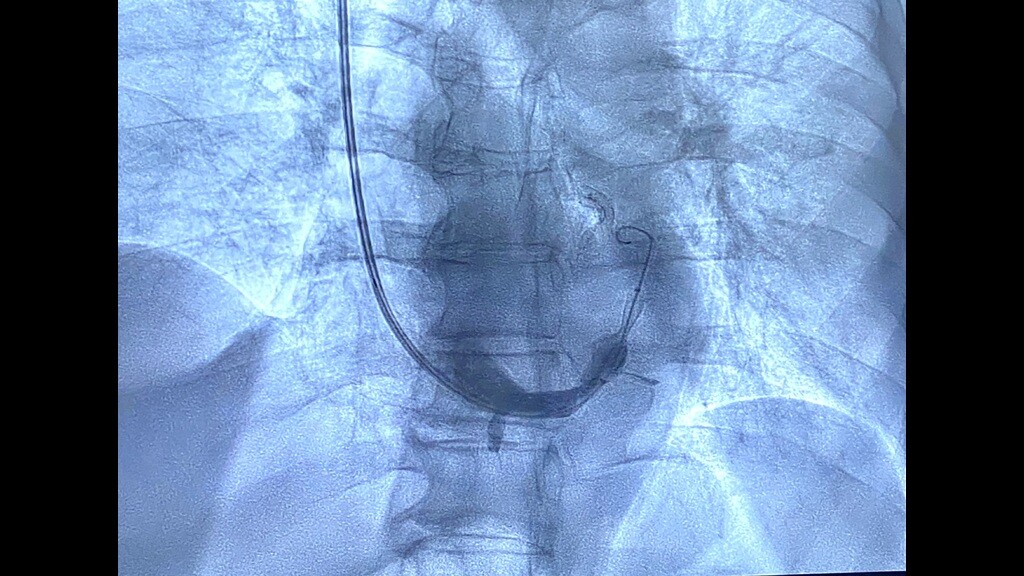

“Abbiamo eseguito questo intervento invasivo ma non chirurgico – ha spiegato Bonfantino - in un paziente di 63 anni, in anestesia locale, che è consistito nell’impianto di uno stent metallico (reducer), a forma di clessidra,  attraverso la vena giugulare, all’interno del seno coronarico, cioè la vena che sbocca nell’atrio destro del cuore e che drena tutto il sangue venoso di origine cardiaca, per poi raggiungere i polmoni ed essere ossigenato.  Questa procedura  - ha aggiunto -trova indicazione in quei pazienti coronaropatici sintomatici, che lamentano angina pectoris nonostante terapie farmacologiche ad alto dosaggio.  La presenza di tale sintomatologia, anche assumendo una terapia farmacologica ottimizzata, determina un aumentato rischio ischemico cardiaco e genera grande frustrazione per i pazienti che non sono quindi in grado di svolgere in serenità le normali attività quotidiane”.

L’impianto dello stent reducer in sala è stato coordinato dal dottor Maurizio Turturo, responsabile della UOS Emodinamica, e dal dottor Francesco Cassano. “Grazie alla particolare morfologia dello stent, a forma di clessidra – ha detto Turturo - si determina un rallentamento del drenaggio venoso cardiaco, permettendo la persistenza nel cuore di sangue ancora ossigenato e quindi il rilascio di una maggiore quantità di ossigeno al muscolo cardiaco. Ciò determina, in un’alta percentuale di casi, la risoluzione dei sintomi anginosi del paziente e il sensibile miglioramento della qualità di vita del paziente”.